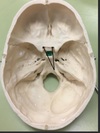

Trochlear Nerve:

Anterior Cranial Fossa, Middle Cranial Fossa, Posterior Cranial Fossa